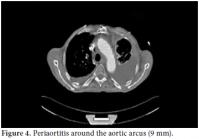

A 61-year-old male patient was admitted to our outpatient unit with dyspnea, edema on the legs, and chest pain. The physical examination was unremarkable except for exophthalmos, tachypnea, S3 edema, and bilateral pretibial pitting edema, and the laboratory investigation revealed the following levels: blood urea nitrogen 94 mg/dL, creatinin 1.38 mg/dL, and C-reactive protein (CRP) 1.53 mg/dl. The anti nuclear antibody (ANA) revealed a negative result. The globulin levels were within normal limits; therefore, IgG and E levels were not analyzed. The patient had no history of autoimmune or allergic diseases. An echocardiographic evaluation was performed to rule out heart failure and massive pericardial effusion, and a mass at the right atrial wall was detected. Nearly 1500 cc pericardial fluid was aspirated by pericardiosynthesis for the relief of the dyspnea. The examinations for tuberculosis revealed negative results, but atypical mesothelial and inflammatory cells were seen in the cytological evaluation. Therefore, computed tomography (CT) of the abdomen and thorax was ordered for further evaluation and pericardial effusion and periaortitis was detected beginning from the arcus and lasting to the abdominal aorta (Figures 1 and 2). On the cardiac CT scan, three soft tissues arising from the right coronary artery and extending to the right atrium were seen (Figure 3). The serologic tests for perinuclear anti-neutrophil cytoplasmic antibodies (p-ANCA) and cytoplasmic anti-neutrophil cytoplasmic autoantibody (c-ANCA) were negative. The radiological evaluation of the exophthalmos with cranial CT revealed bilateral retro-orbital pseudotumors, although the thyroidstimulating hormone level was normal (Figure 4). By all of these radiological findings, IgG4-related sclerosing vasculitis was first suspected, and the level of IgG4 was found to be 148 (0-125) U/ml. The patient was referred to the cardiovascular surgeons for a biopsy from the mass in the right atrium. The histological evaluation of the biopsy material revealed lymphoplasmacytic infiltration fibrosis, a lymphoid follicle, and eosinophilic infiltration. These findings were concordant with IgG4-related sclerosing vasculitis. The arterial constrictions in the right coronary artery and circumflex artery were removed by percutaneous balloon angioplasty and two cardiac stents a cardiac pacemaker were implanted.

The appropriate treatment was ordered as a pulse steroid of 1000 mg prednisolone and 500 mg cyclophosphamide every month in conjunction with oral immunosuppressive therapy. A radiological evaluation after three months revealed significant response and regression of the lesions. The mass in the right atrium had decreased to 16 mm, and the lesion on the retro-orbital area had decreased to 11 mm on the right and 12 mm on the left.